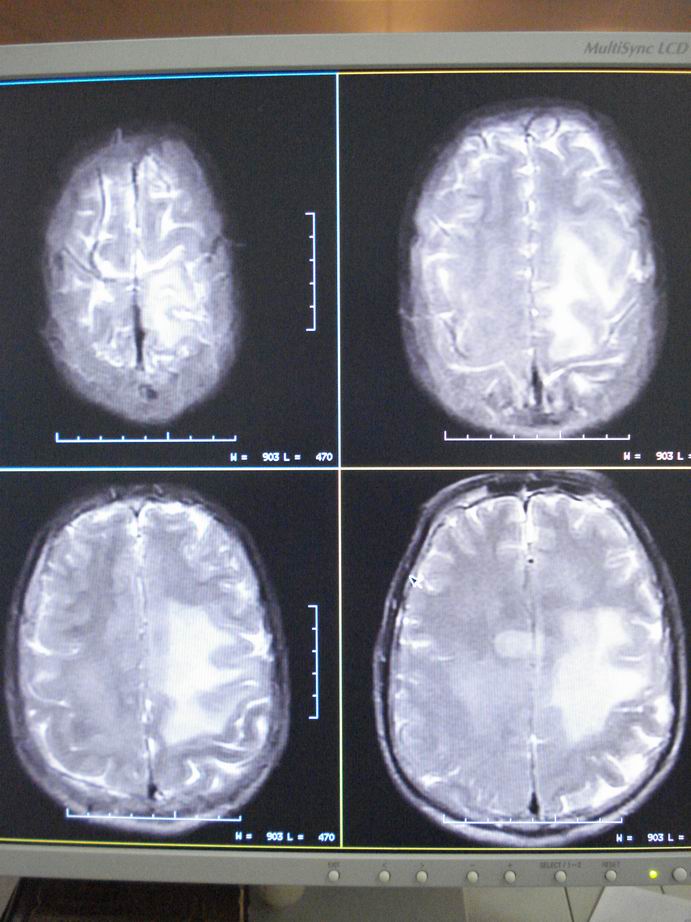

男60岁,左侧肢体乏力及精神异常10天,血压正常,血常规,肝肾功正常,腰穿无异常,请教颅内多发病灶,考虑什么?感染?肿瘤(转移性?)还是其它?

考虑为颅内多发转移瘤

脑内多发性转移瘤。

淋巴瘤较转移瘤可能大。

脑内多发占位性病变,首先考虑感染性病变,其次是转移瘤。

结合病人高龄,考虑转移瘤